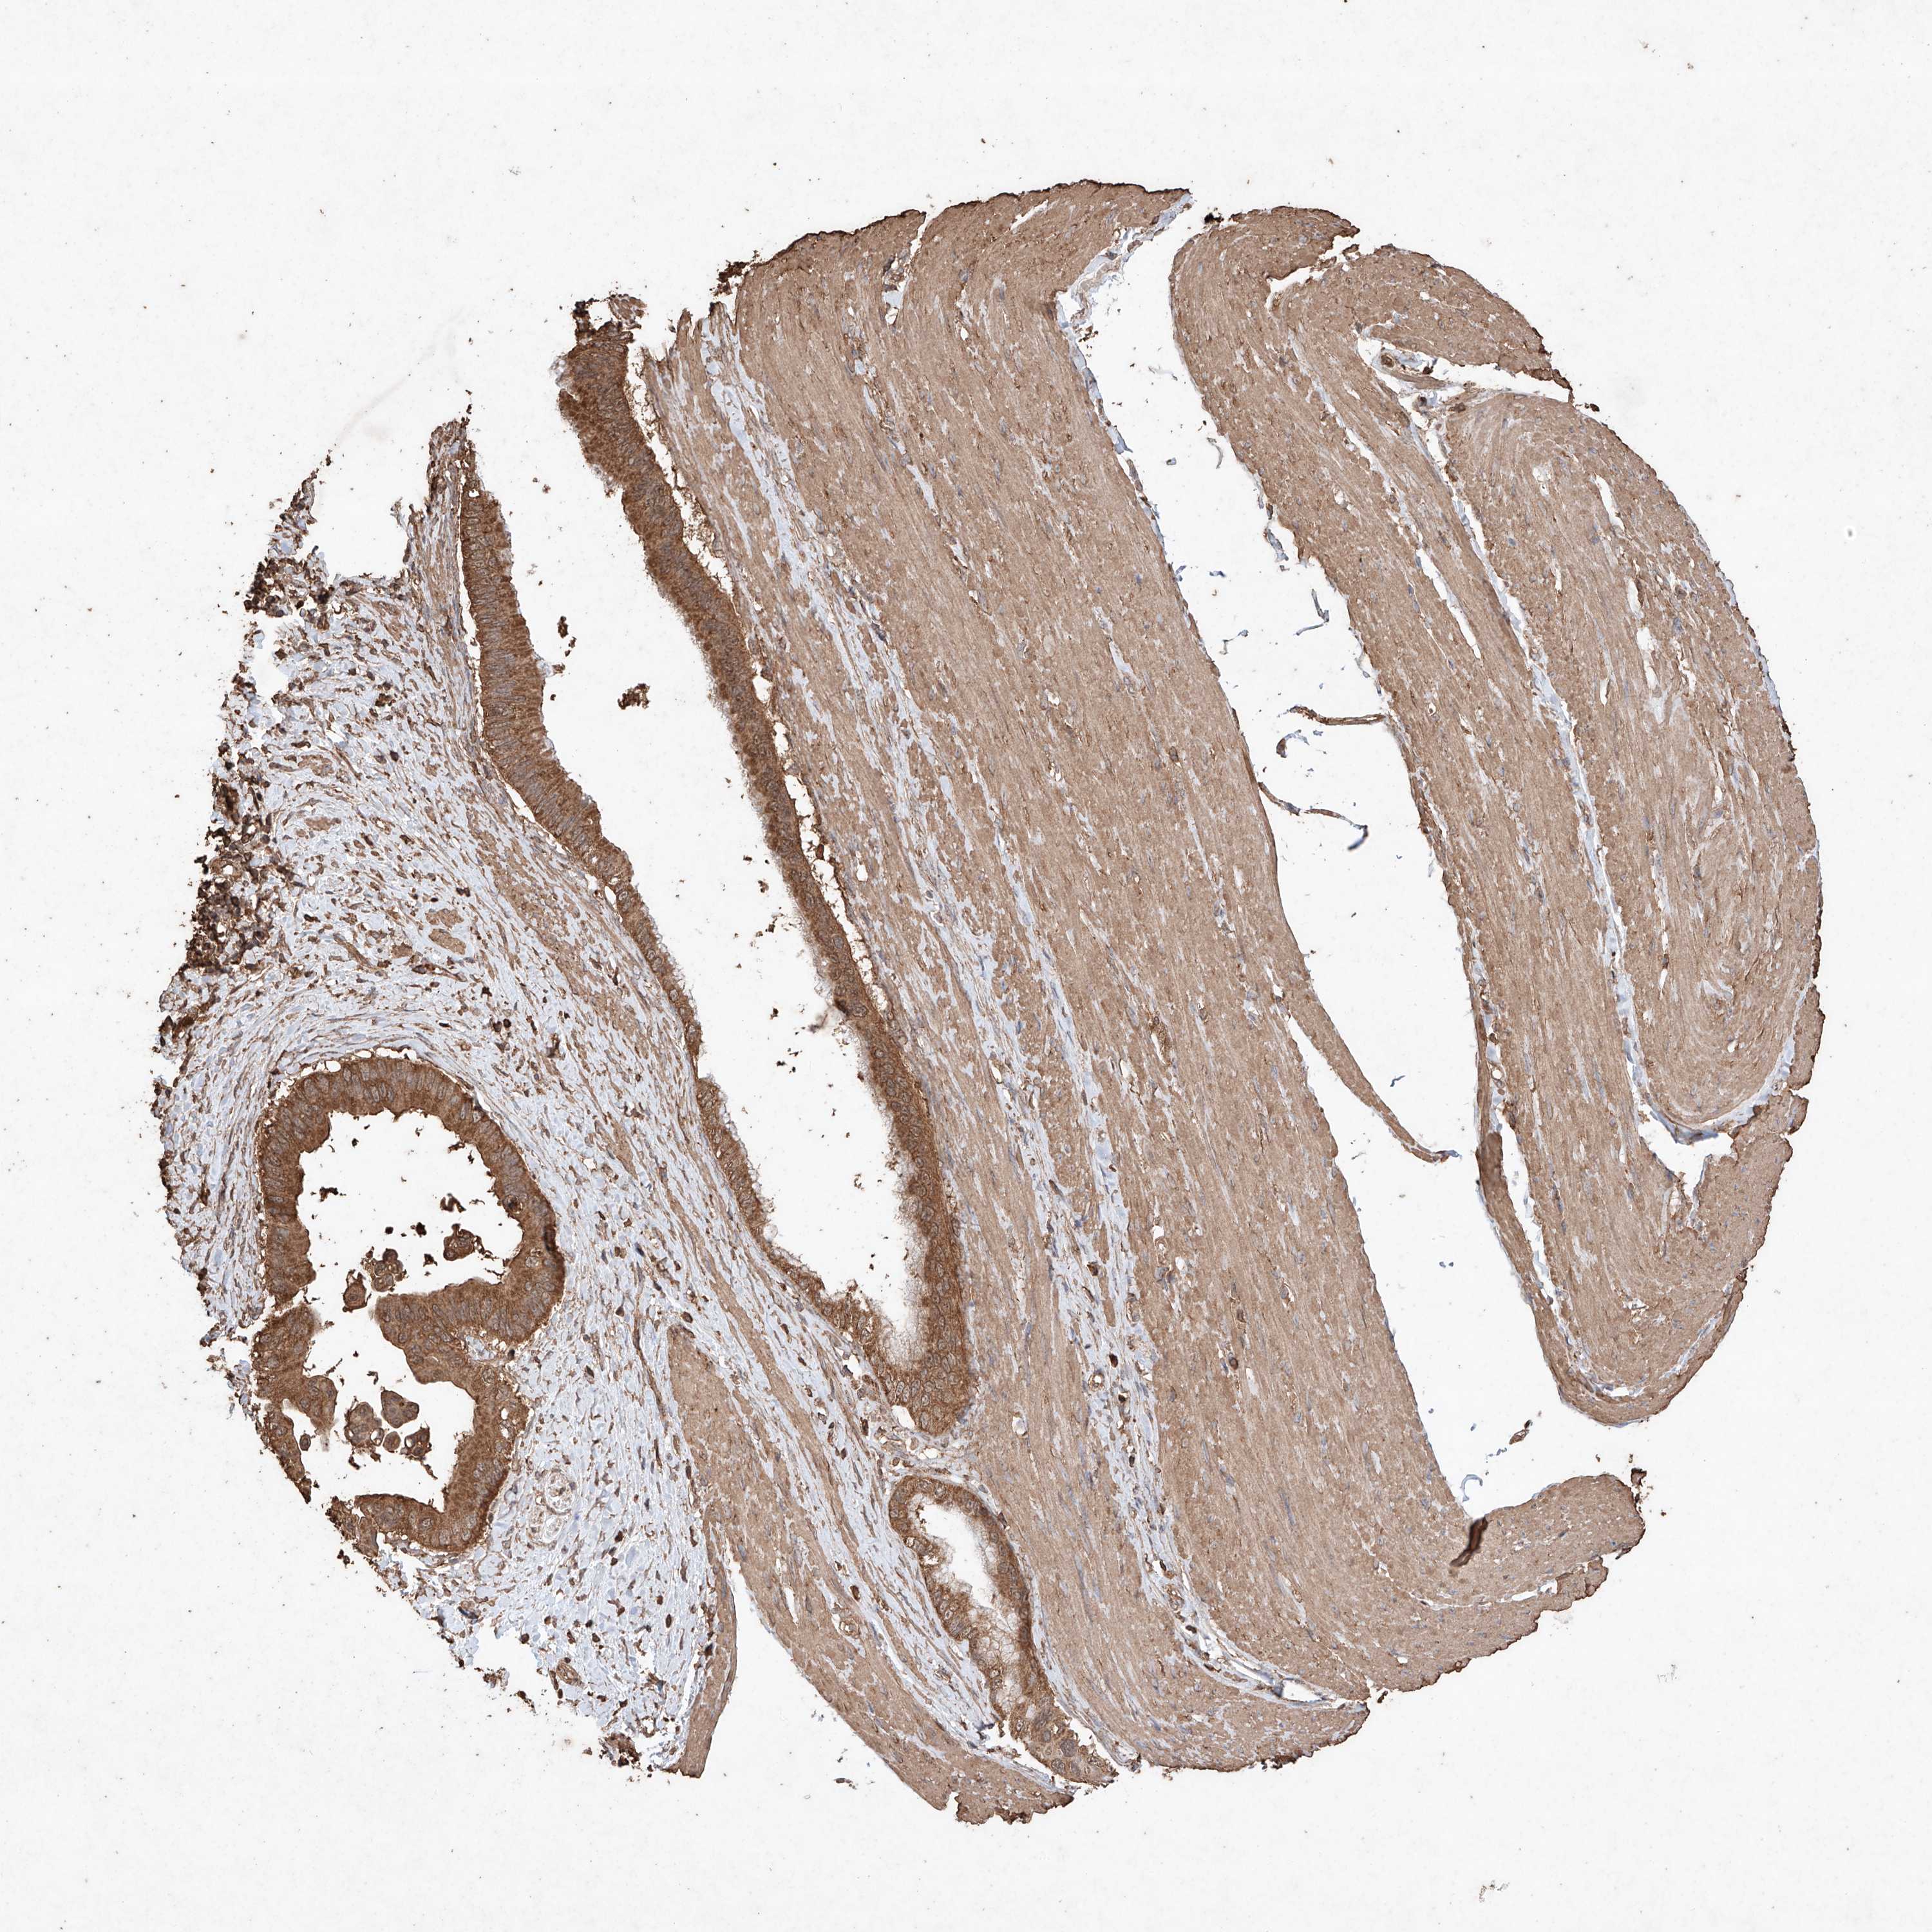

PANCREATIC CANCER - Protein expressioni

A mouse-over function shows sample information and annotation data. Click on an image to view it in a full screen mode. Samples can be filtered based on level of antibody staining by selecting one or several of the following categories: high, medium, low and not detected. The assay and annotation is described here.

Note that samples used for immunohistochemistry by the Human Protein Atlas do not correspond to samples in the TCGA dataset.

Antibody stainingi

Antibody staining in the annotated cell types in the current human tissue is reported as not detected, low, medium, or high, based on conventional immunohistochemistry profiling in selected tissues. This score is based on the combination of the staining intensity and fraction of stained cells.

Each image is clickable and will lead to virtual microscopy that enables deeper exploration of all samples and also displays staining intensity scores, fraction scores and subcellular localization as well as patient and tissue information for each sample.

Antibody HPA040445

Antibody CAB034464

Staining

High

Medium

Low

Not detected

Intensity

Strong

Moderate

Weak

Negative

Quantity

>75%

75%-25%

<25%

None

Location

Nuclear

Cytoplasmic/membranous

Cytoplasmic/membranous,nuclear

Adenocarcinoma, NOS